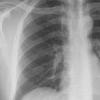

Normal PA

24 yo male

Date: 06/08/2016

Views: 6327